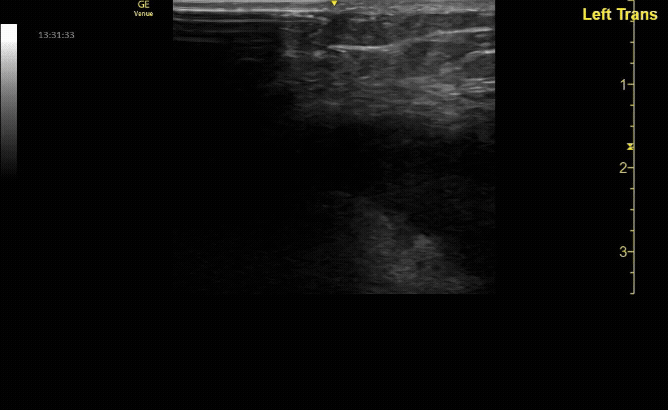

Extensor tenosynovitis in a patient following a cat bite.

Necrotizing fasciitis. Note air under the tendon.